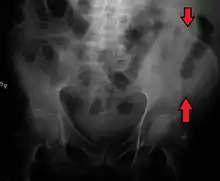

The crest of the ilium (or iliac crest) is the superior border of the wing of ilium and the superiolateral margin of the greater pelvis.

The iliac crest stretches posteriorly from the anterior superior iliac spine (ASIS) to the posterior superior iliac spine (PSIS). Behind the ASIS, it divides into an outer and inner lip separated by the intermediate zone. The outer lip bulges laterally into the iliac tubercle.[1] Palpable in its entire length, the crest is convex superiorly but is sinuously curved, being concave inward in front, concave outward behind.[2]

Iliac crest labeled at center right

Iliac crest